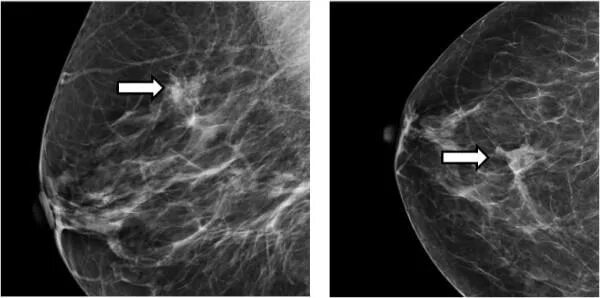

Что значит кальцинат в молочной железе